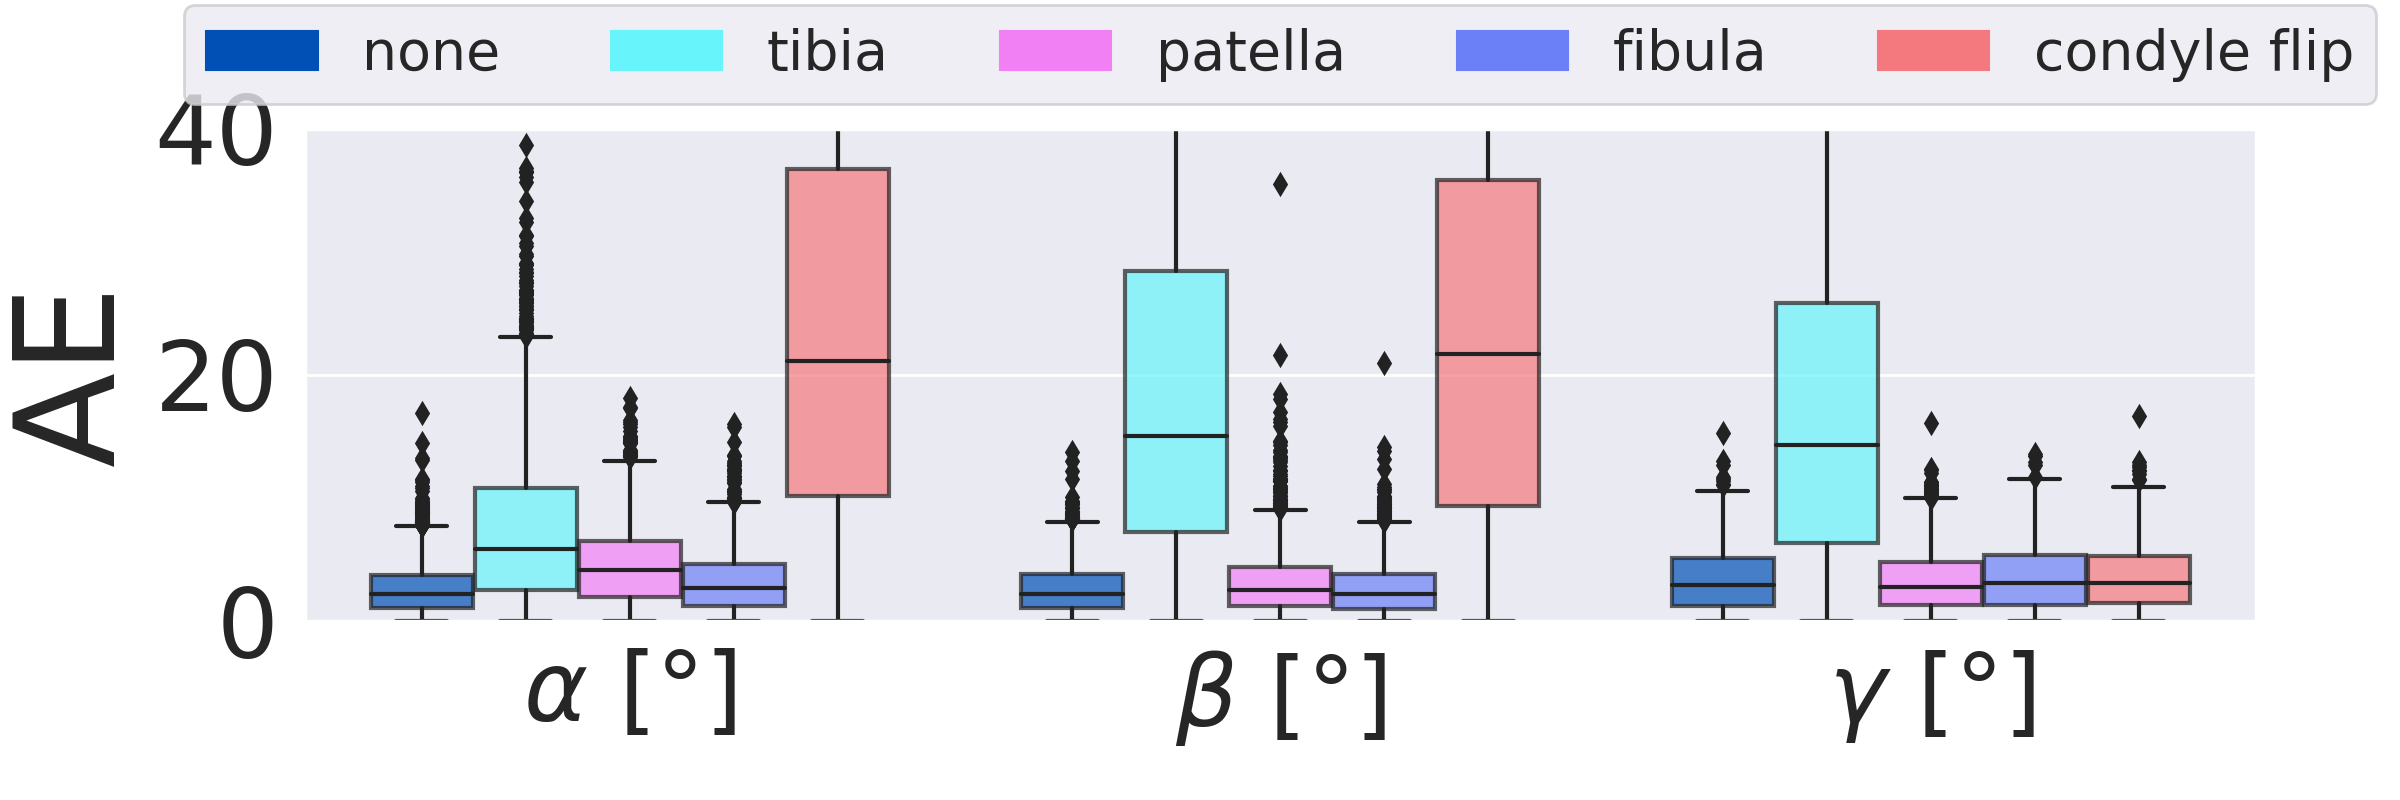

3.2 Importance of individual bones on overall performance (RQ2)

Fig. 7 shows the importance of individual segmented bone classes on the overall positioning performance evaluated on the test DRRs (3528 DRRs). The fibula has very little influence on the positioning for both views. The patella is only important for the a.-p. view, while tibia and femur are relevant for both views. The condyle assignment for the lateral view determines the rotation direction for the orbital and angular rotation (, ). Inverting the assignment of left and right femur condyle results in a sign flip in , .